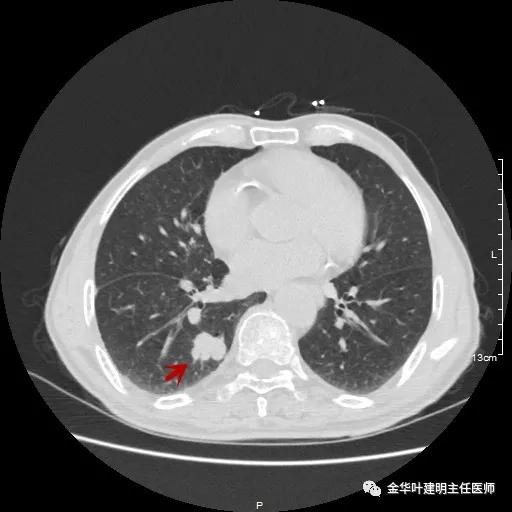

以上示右下叶病灶5。也是主病灶,是实性块状分叶的占位性病变,基本可以肯定是肺癌。单病灶看需下叶切除并清扫淋巴结。

以上示右下叶病灶6。同样是囊腔型病灶,但较前几个范围小,可囊壁同样为磨玻璃影,也是较为典型的囊腔型肺癌表现,单灶来看可下叶背段切除。

如此多的病灶,这样的年纪该如何考虑?我们先来分一下:病灶3与病灶5是混合磨玻璃及实性病灶,不能继续观察等待,得干预;病灶1、病灶4与病灶6是囊腔型肺癌考虑,恶性程度低,可观察随访,若处理病灶3与5的话,能附带则要附带处理;病灶2在左侧,目前较小,而且在肺外周部位,若对右侧进行干预,则左侧先观察随访,下次可考虑局部楔形切除。